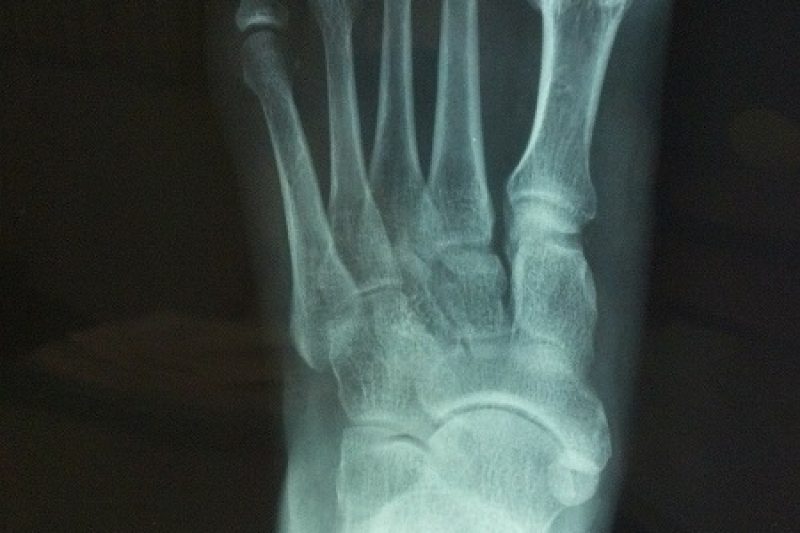

The foot is a complex structure consisting of several small bones, muscles, tendons, and other soft tissues responsible for bearing your weight and helping you navigate the world around …

Foot and ankle injuries are unfortunately very common. These types of injuries often occur when the ligaments that support the foot or ankle stretch beyond their limits and tear. …